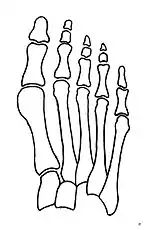

Fig. 8a. Painful hallux valgus and metatarsus primus varus deformity recurrence of left foot after osteotomy surgery | |

- For recurrence correction after osteotomy procedure (Fig. 8)

Late deformity recurrence can happen after osteotomy (bone-breaking) procedures because osteotomy surgeries do not specifically stabilize first metatarsal bone.